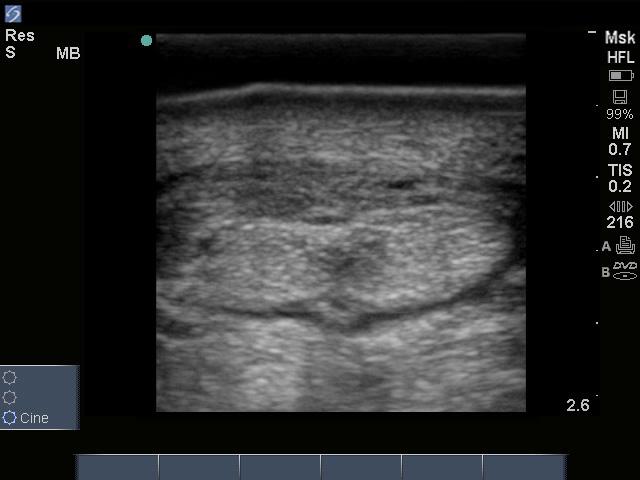

The most striking anatomic difference is observed when trying to give jugular injections or place catheters. While the jugular vein lies in the same position as in the horse, donkey skin is thicker, and there is a thick layer of fascia covering the entire neck (Figure 1). It is like hitting the jugular on a cow. Add to this the fact that donkeys and mules don’t tolerate numerous attempts to hit the vein. This author (NM) has had good luck giving Dormosedan gel to unhandled donkeys and mules (at the horse-label dose) to provide sedation prior to anesthesia (Figure 2).

Figure 2: This author (NM) has had good luck giving Dormosedan gel to unhandled donkeys and mules (at the horse-label dose) to provide sedation prior to anesthesia. Image courtesy of Drs. Nora Matthews and Jill K. Maney. Figure 1: While the jugular vein lies in the same position as in the horse, donkey skin is thicker and there is a thick layer of fascia covering the entire neck.